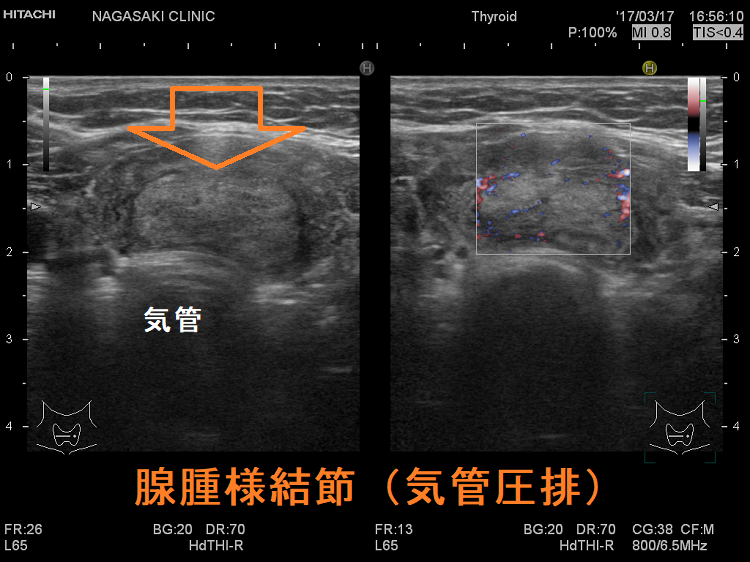

腺腫様甲状腺腫

腺腫様甲状腺腫でも咽喉頭圧排と浮腫により、閉塞性睡眠時無呼吸症候群(OSAS)を引き起こします。甲状腺全摘出で改善(J Laryngol Otol. 2012 Feb;126(2):190-5.)。

ケース①